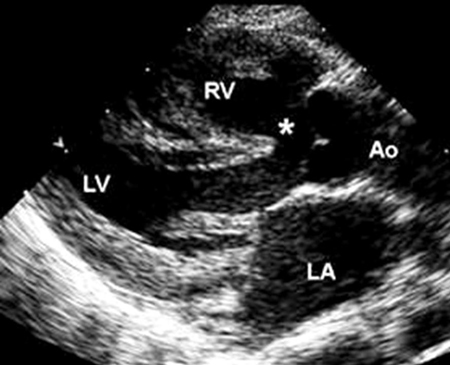

Imagem de ecocardiografia do eixo paraesternal longo em um paciente com tetralogia de Fallot. A aorta (Ao) sobrepõe-se ao defeito do septo ventricular (DSV) (*). (AE) átrio esquerdo; (VD) ventrículo direito; (VE) ventrículo esquerdo

Imagem cedida por Patrick W. O'Leary, MD